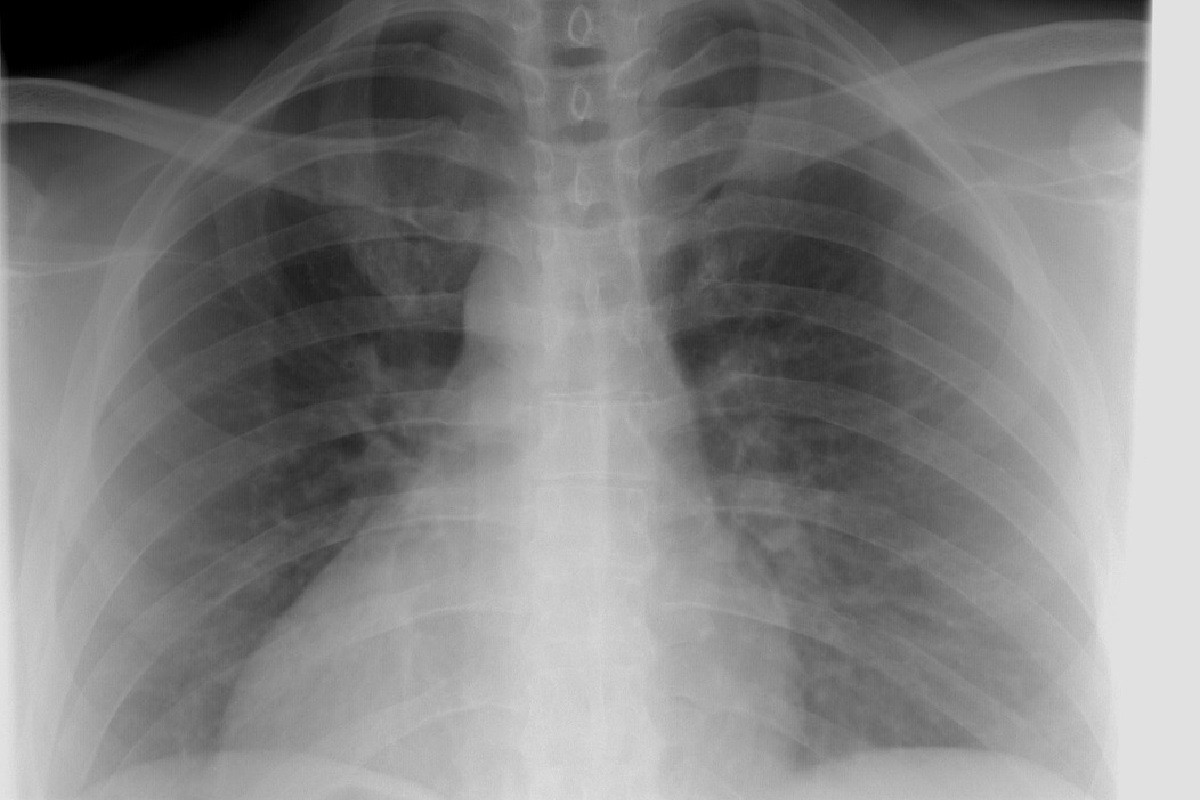

Η μελέτη κατέδειξε ότι η θεραπεία επιβράδυνε την ανάπτυξη των βακτηρίων, ενίσχυσε τις ανοσολογικές αποκρίσεις και μείωσε τη βλάβη των πνευμόνων σε προκλινικά μοντέλα πολυανθεκτικής πνευμονίας. Αυτό αποδείχτηκε μέσα από μελέτες σε ποντίκια και δοκιμές με ανθρώπινο πνευμονικό ιστό στο εργαστήριο.

Σε μοντέλα ποντικών με πολυανθεκτικό Staphylococcus aureus και Pseudomonas aeruginosa, οι επαναλαμβανόμενες δόσεις της θεραπείας ήταν καλά ανεκτές. Η θεραπεία μείωσε το βακτηριακό φορτίο στους πνεύμονες, τη φλεγμονή και βοήθησε στη διατήρηση μιας υγιούς πνευμονικής δομής.

Δοκιμές σε ανθρώπινο πνευμονικό ιστό παρήγαγαν παρόμοια αποτελέσματα, δείχνοντας ότι το mRNA που παράγει πεπτιδοσώματα θα μπορούσε να λειτουργήσει αποτελεσματικά παράλληλα με τα ανθρώπινα ανοσοκύτταρα.